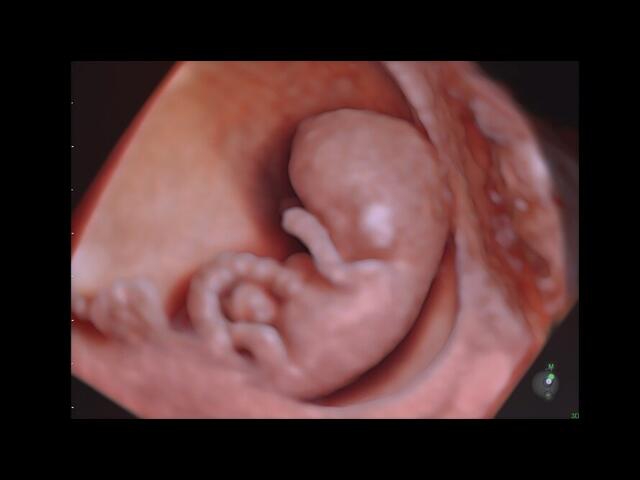

• HDlive: Технология HDlive обеспечивает анатомический реализм и высокую точность диагностики, позволяя совмещать несколько независимых источников света для создания оттенков и теней.

HDlive:

Да